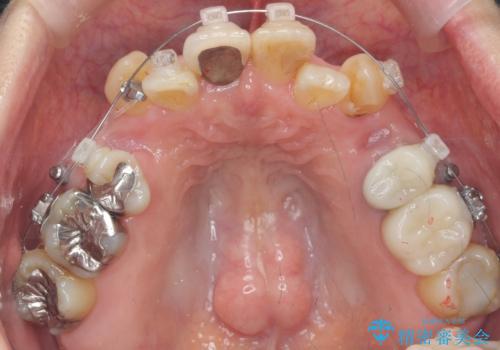

50代女性 八重歯を矯正治療 歯並びの中等度のがたつき

- ワイヤー矯正

- 八重歯の矯正を希望されて来院。

歯は入りきらないため、通常の抜歯矯正を行いました。

歯がご年齢的に動きにくいため、被せ物のやり替えを含めて治療期間の短縮を図りました。

矯正治療自体は2年半、虫歯治療等で1年ほどかかっています。

詰め物や被せ物のやり替えも併せて行っているため、治療期間を比較的短縮できました。